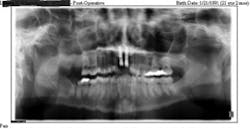

One year after the crowns were replaced, the teeth became mobile. The patient went in for an appointment and radiographs confirmed external root resorption had occured around the reimplanted teeth (refer to figure 3).

The root resorption in this case was most likely due to PDL damage. Treatment options were explained and the decision was made to extract the teeth and place dental implants. She was referred to a Mankato, Minnesota oral surgeon for the implants.